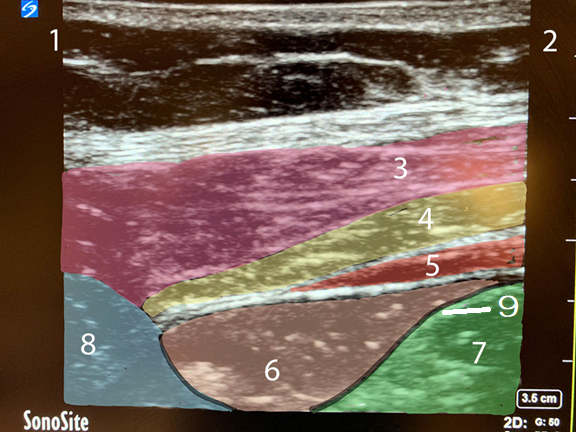

QL Block Lateral Approach Image